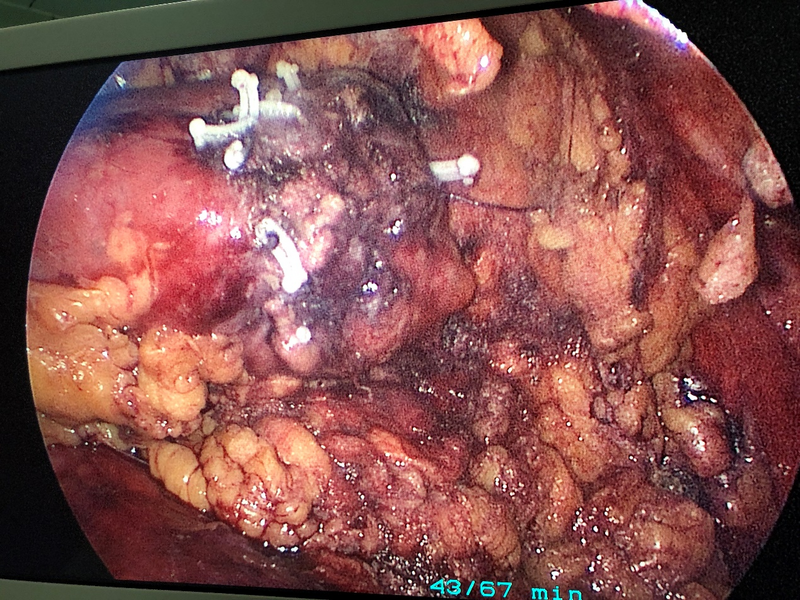

近日,市人民醫(yī)院泌尿外科對一例高齡腎腫瘤患者采用單孔腹腔鏡技術(shù),通過腰部長約3cm左右小切口,成功實施了全市首例單孔腹腔鏡下右腎部分切除手術(shù)。此舉標(biāo)志著泌尿外科單孔腹腔鏡技術(shù)再上新臺階。

患者入院后,手術(shù)團(tuán)隊積極完善術(shù)前檢查,并針對已有病史做好應(yīng)急預(yù)案,之后行經(jīng)腰單孔腹腔鏡下右腎部分切除手術(shù)。手術(shù)順利歷時2小時,腫瘤切除完整,腎臟創(chuàng)面縫合佳,術(shù)中出血不到50ml,術(shù)后8小時患者腸道恢復(fù)通氣,第三天拔除引流管,術(shù)后1周病理結(jié)果顯示血管平滑肌脂肪瘤,現(xiàn)患者已康復(fù)出院。